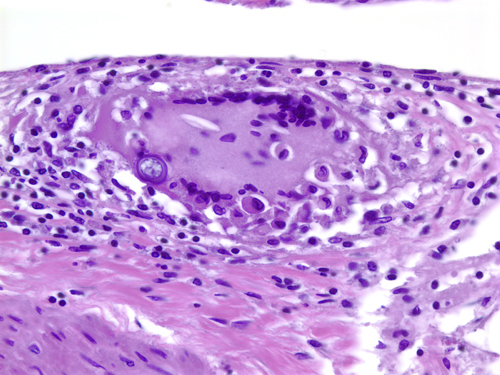

Cysticercosis is the most common parasitic infection and neurocysticercosis is the most common cause of secondary seizures worldwide. Cysticercosis is caused by ingestion of water, vegetables and other foods fecally contaminated by eggs excreted by carriers of the pork tapeworm, Taenia Solium. In the intestine, the eggs transform into oncospheres which penetrate the intestinal wall, enter the circulation and lodge in the brain, eyes, muscles and other tissues. There, oncospheres develop into cysticerci. The same sequence occurs in pigs, which are the intermediate host of T. solium. In pigs, cysticercosis affects primarily muscles. After consumption of pork containing cysticerci, scolices attach to the small intestinal wall and develop into adult worms. This condition is called intestinal taeniasis. Eggs or proglotids of the adult worms are then shed in the feces, contaminating the environment.